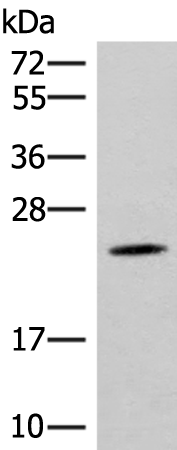

分类: 科研抗体货号: P03057别名: MDS023; MRPS28; MRP-S28; HDCMD11P应用: WB,IHC反应种属: Human